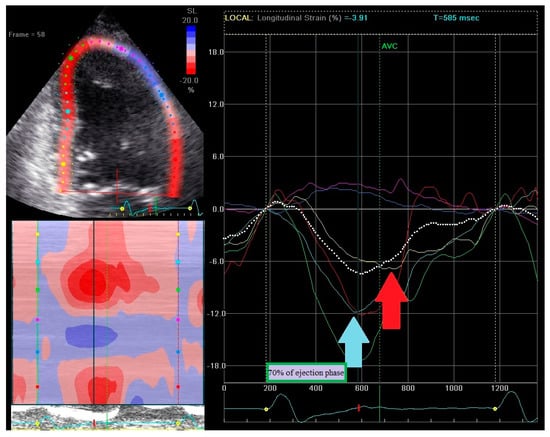

- (1)

- Early contraction of at least one basal or midventricular segment in septal or anteroseptal wall and early stretching in at least one basal or midventricular segment in the opposing wall,

- (2)

- the early peak contraction does not exceed 70% of the ejection phase,

- (3)

- the early stretching wall shows a peak contraction after aortic valve closure.